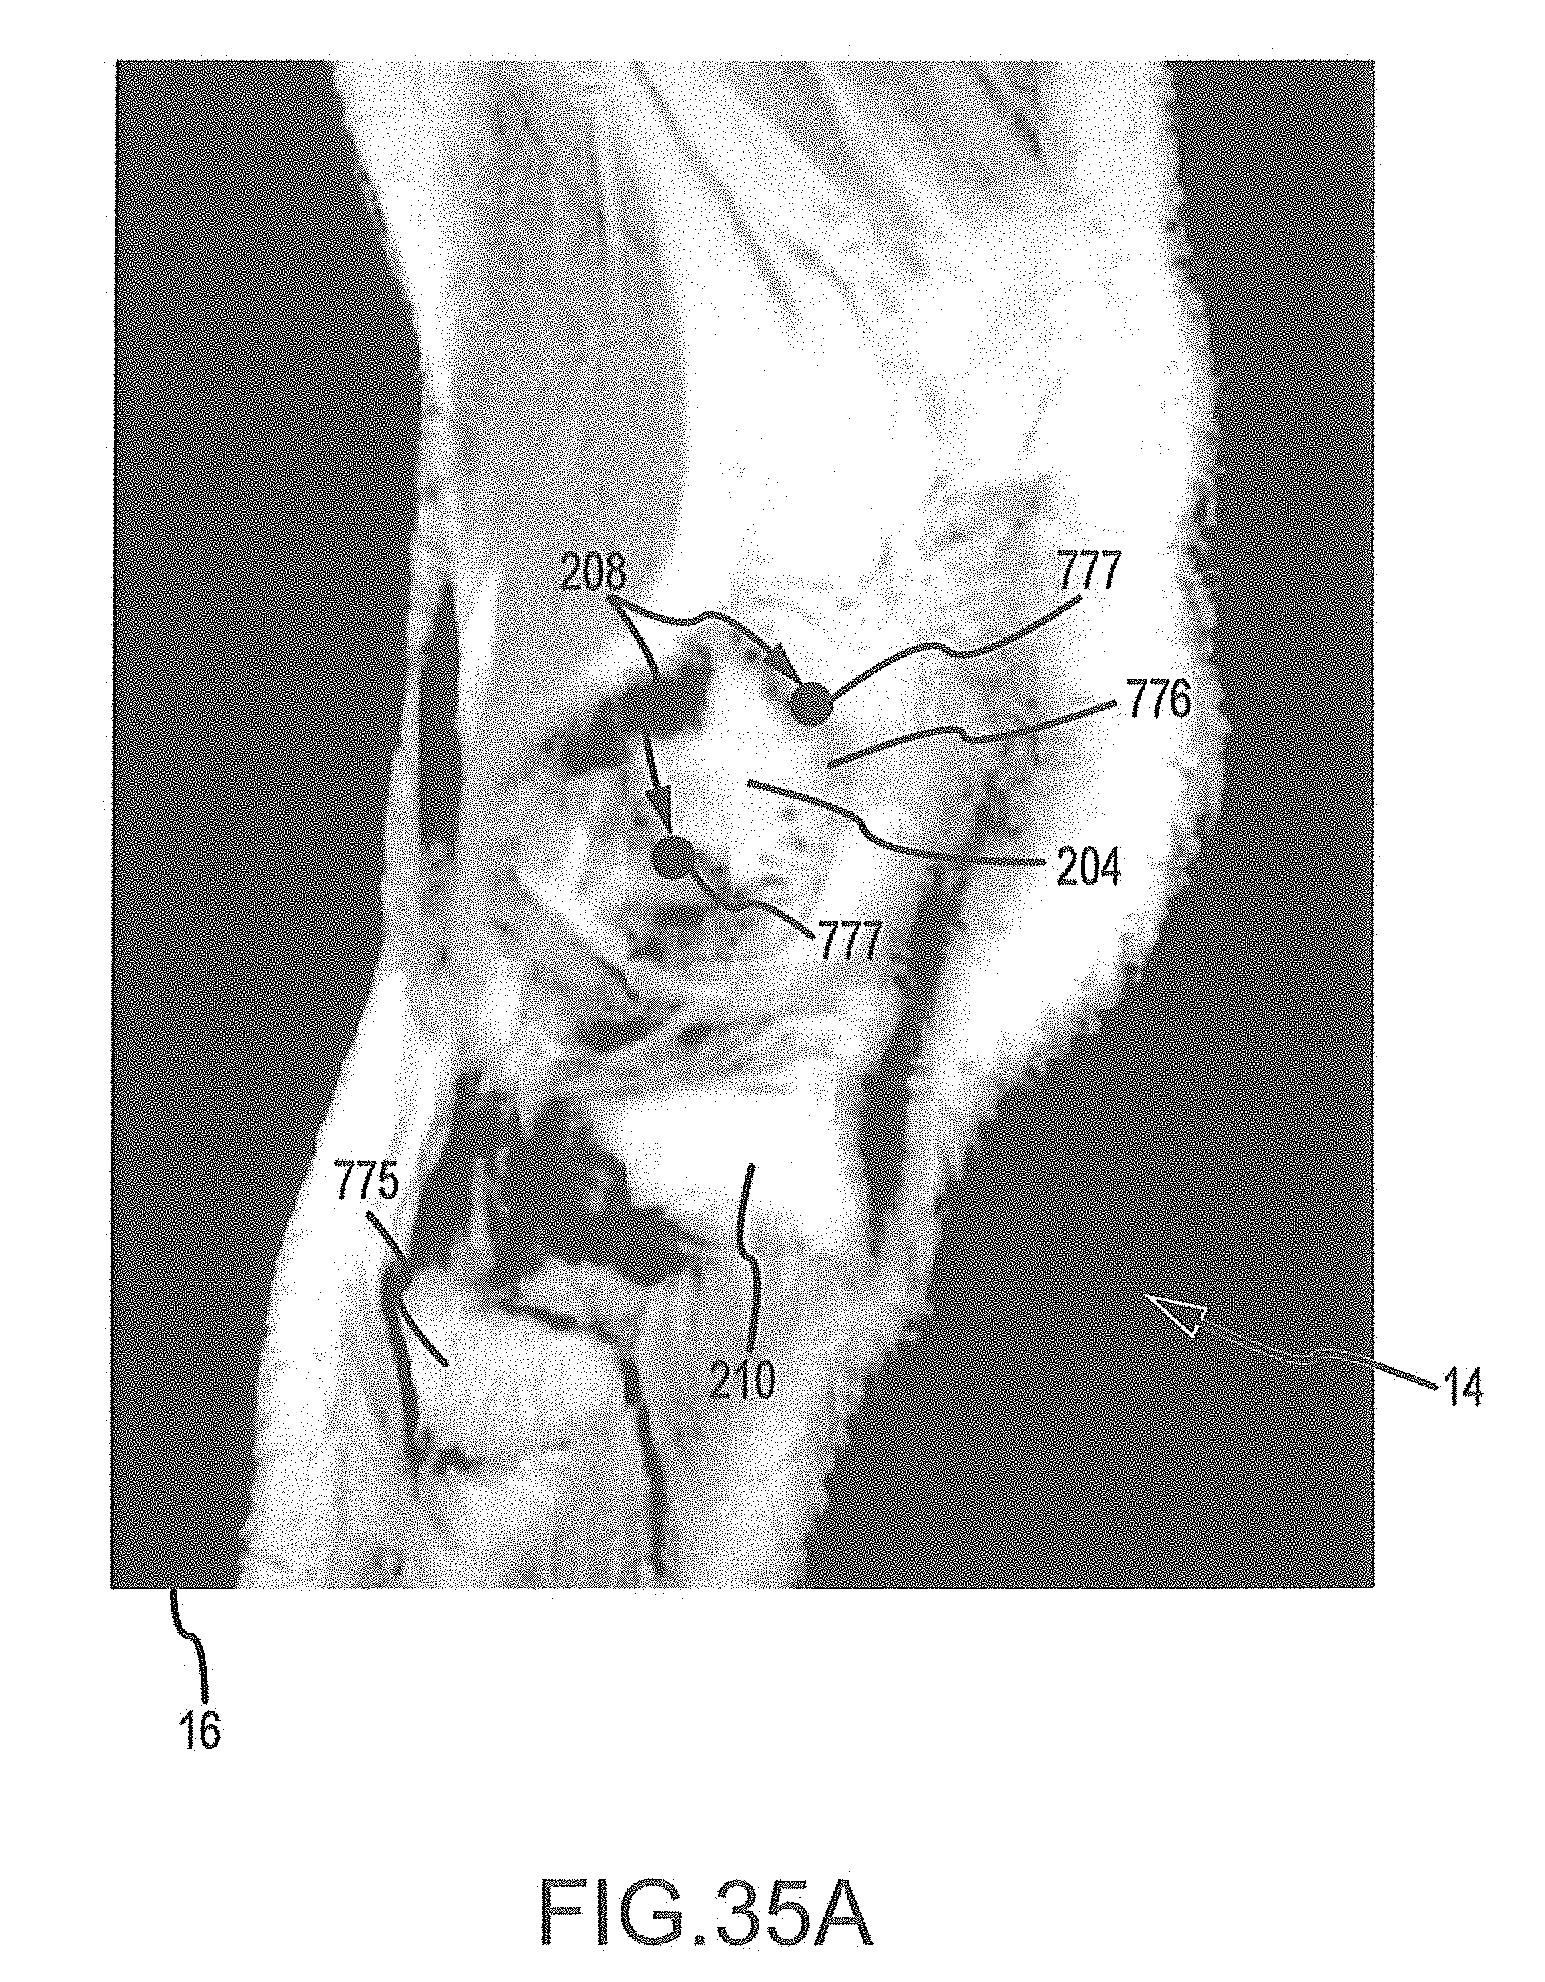

FIGS. 35A-35H are a series of sagittal image slices wherein landmarks have been placed according the process of FIG. 34.

The imager 8 typically generates a plurality of image slices 16 via repetitive imaging operations. Depending on whether the imager 8 is a MRI or CT imager, each image slice will be a MRI or CT slice. As shown in FIG. 2A, the image slice may depict the cancellous bone 200, the cortical bone 202 surrounding the cancellous bone, and the articular cartilage lining portions of the cortical bone 202 of an object of interest of a joint, e.g., a femur 204 in a patient's knee joint 14. The image may further depict the cancellous bone 206, the cortical bone 208 of another object of interest in the joint, e.g., a tibia 210 of the knee joint 14. In one embodiment, each image slice 16 may be a two-millimeter 2D image slice.